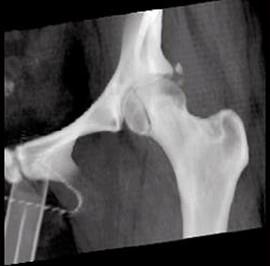

问题 女,35岁,摔伤后左髋部剧痛,活动受限6小时,请结合影像学检查,选出最可能的诊断 ( )

选项 A、加莱阿奇骨折 B、肱骨骨折 C、股骨头骨折 D、骨盆骨折 E、股骨颈骨折

答案 C